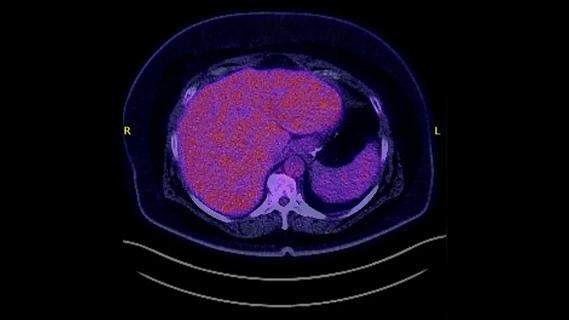

Preoperative computed tomography shows extensive bilobar liver metastases from colorectal cancer.